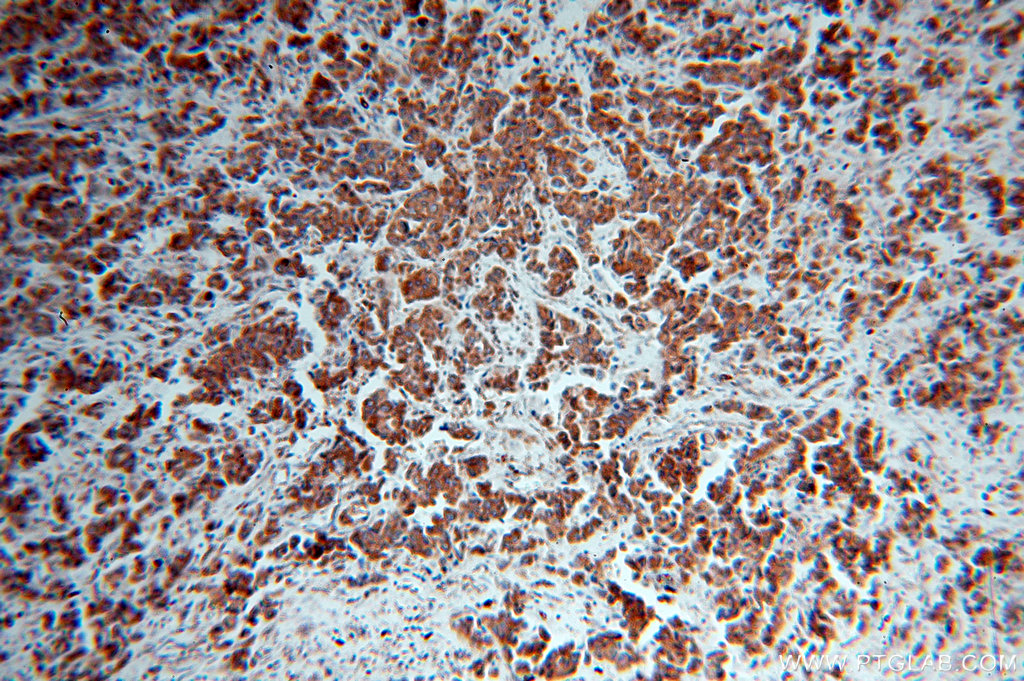

IRS1抗体

产品名称: IRS1抗体

英文名称: IRS1Antibody

产品编号: XY17509-1

使用范围: WB,ELISA,IHC-P,IHC-F,IF